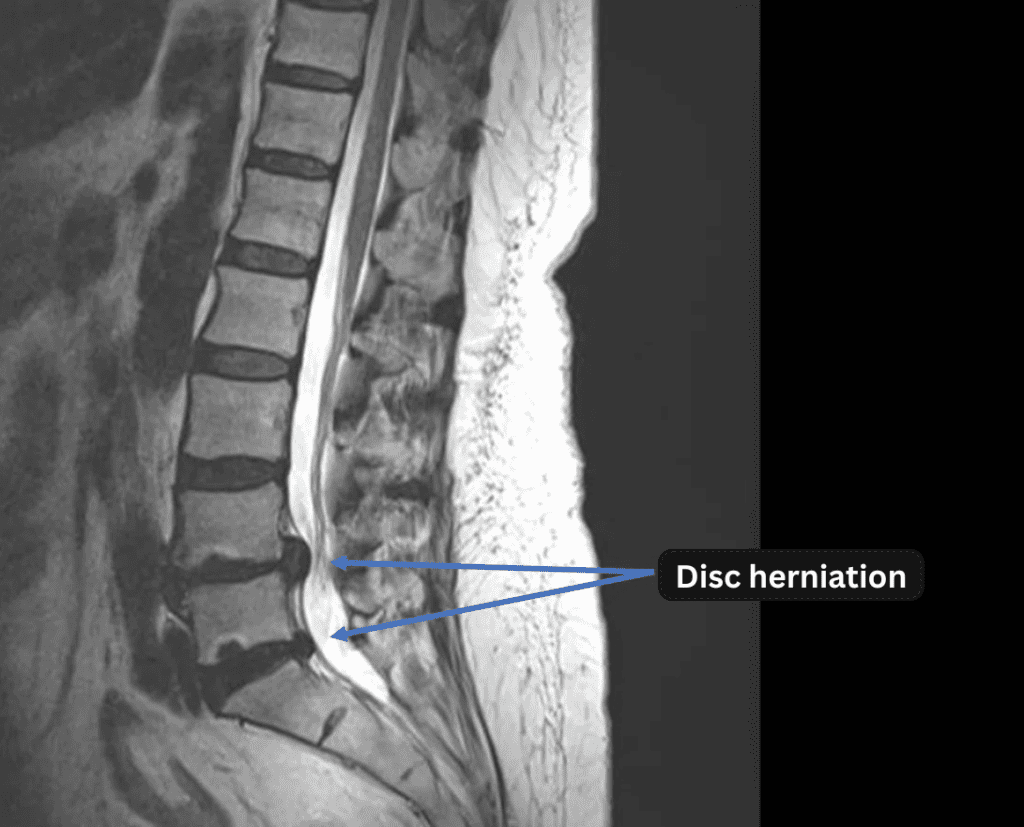

Imaging and findings

- L3/4, L4/5, L5/S: Disc degeneration

- L4/5, L5/S: Disc herniation

The above findings were also observed on the imaging.

・These findings suggest that the herniation at L4/5 and L5/S is the most likely cause of the patient’s symptoms.